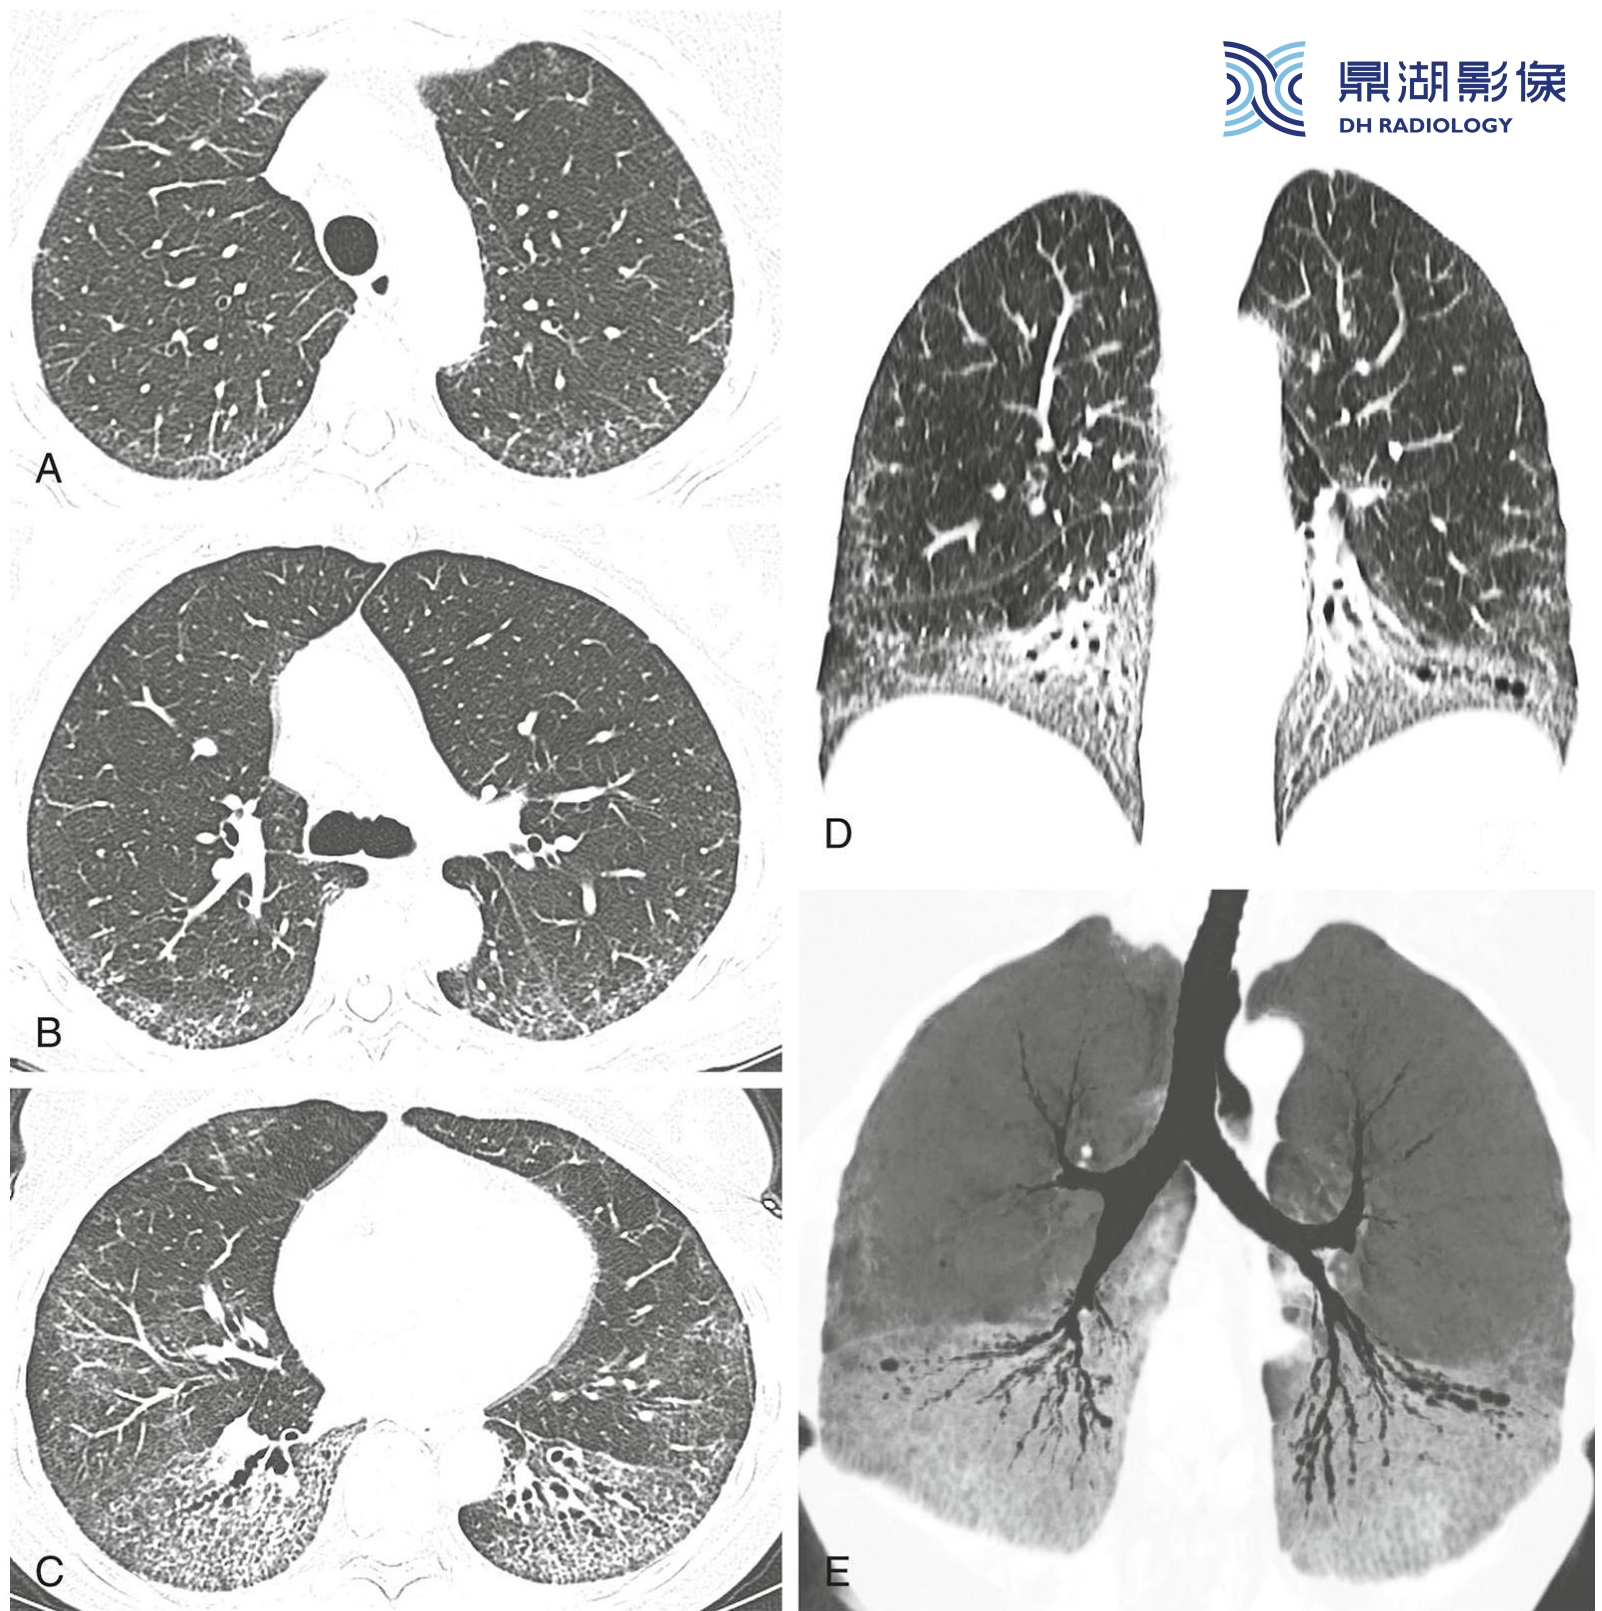

普通型间质性肺炎的分布。

经主动脉弓(A)、气管隆嵴(B)及肺基底(C)平面的HRCT显示胸膜下和肺基底分布为主的蜂窝征。冠状位(D)和冠状位最小强度投影(MIP)重组(E)均明确显示了位于肺基底的病变。